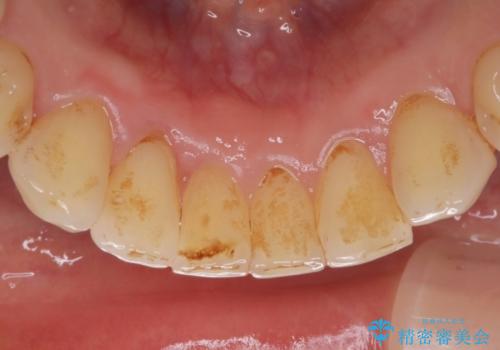

- インビザラインで矯正中の患者様です。リファインメントのタイミングでホームホワイトニングをご希望でしたが、歯の表面にステインがかなり付着していたため、エアフローでのクリーニングからお勧めしました。

歯の表面にステインやバイオフィルムが付着していると、歯面がざらつき更に汚れが付きやすくなるだけでなく、付着物の影響でホワイトニング薬剤の浸透が悪くなりトーンアップ効果が減少します。歯の表面の汚れを落とすことで歯面もツルツルになり、ホワイトニングを行わなくても歯が白くなった様に感じられる場合もあります。